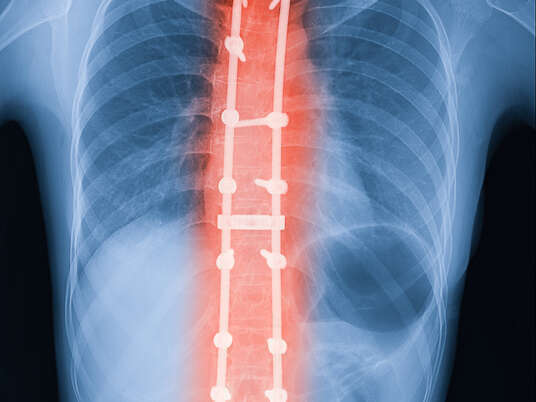

La chirurgie de la scoliose, qui implique principalement la fusion vertébrale, vise à corriger la scoliose et à stabiliser la colonne vertébrale.

Au cours de l'intervention, le chirurgien aligne les vertèbres affectées, puis les fusionne à l'aide de greffes osseuses, de tiges métalliques et de vis. Ces composants aident à maintenir la colonne vertébrale droite pendant que les greffes osseuses se développent et se solidifient en un seul os solide. L'intervention chirurgicale s'adresse généralement aux sections les plus touchées de la colonne vertébrale.